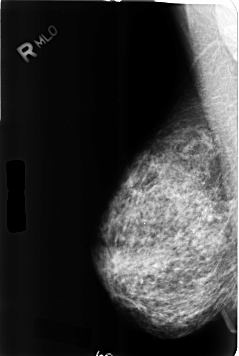

ics_version 1.0 filename B-3357-1 DATE_OF_STUDY 25 7 1995 PATIENT_AGE 55 FILM FILM_TYPE REGULAR DENSITY 3 DATE_DIGITIZED 13 7 1998 DIGITIZER LUMISYS LASER SEQUENCE LEFT_CC LINES 4664 PIXELS_PER_LINE 3096 BITS_PER_PIXEL 12 RESOLUTION 50 OVERLAY LEFT_MLO LINES 4640 PIXELS_PER_LINE 3080 BITS_PER_PIXEL 12 RESOLUTION 50 OVERLAY RIGHT_CC LINES 4608 PIXELS_PER_LINE 3072 BITS_PER_PIXEL 12 RESOLUTION 50 NON_OVERLAY RIGHT_MLO LINES 4624 PIXELS_PER_LINE 3096 BITS_PER_PIXEL 12 RESOLUTION 50 NON_OVERLAY |